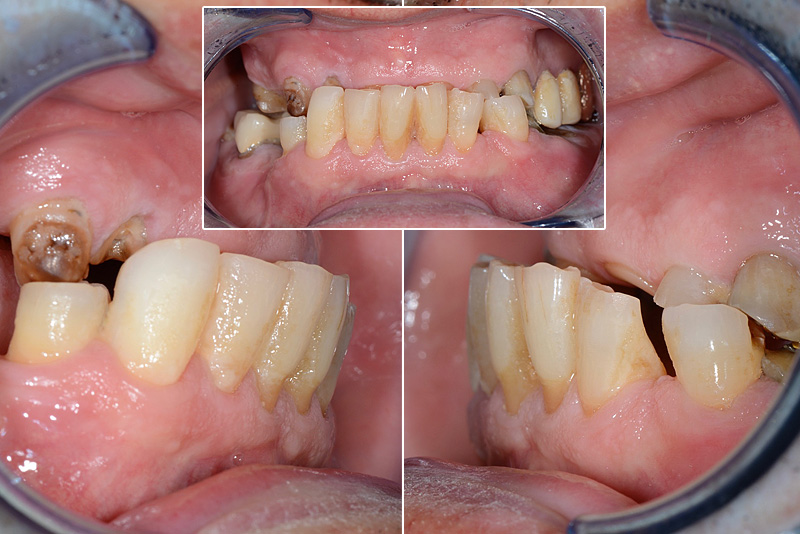

PREMESSA: in seguito all’estrazione dell’incisivo laterale superiore di destra, resasi necessaria per cause batteriche, si decide di affrontare il caso con il posizionamento di un impianto in sostituzione dell’elemento mancante dopo guarigione del sito infetto. Con tecniche rigenerative sia dei tessuti ossei mancanti a causa dell’infezione pregressa, sia dei tessuti gengivali che appaiono inizialmente troppo spostati in alto, si ripristina una corretta morfologia delle parabole (contorni) gengivali e delle papille interdentali (triangoli di gengiva tra due denti vicini).